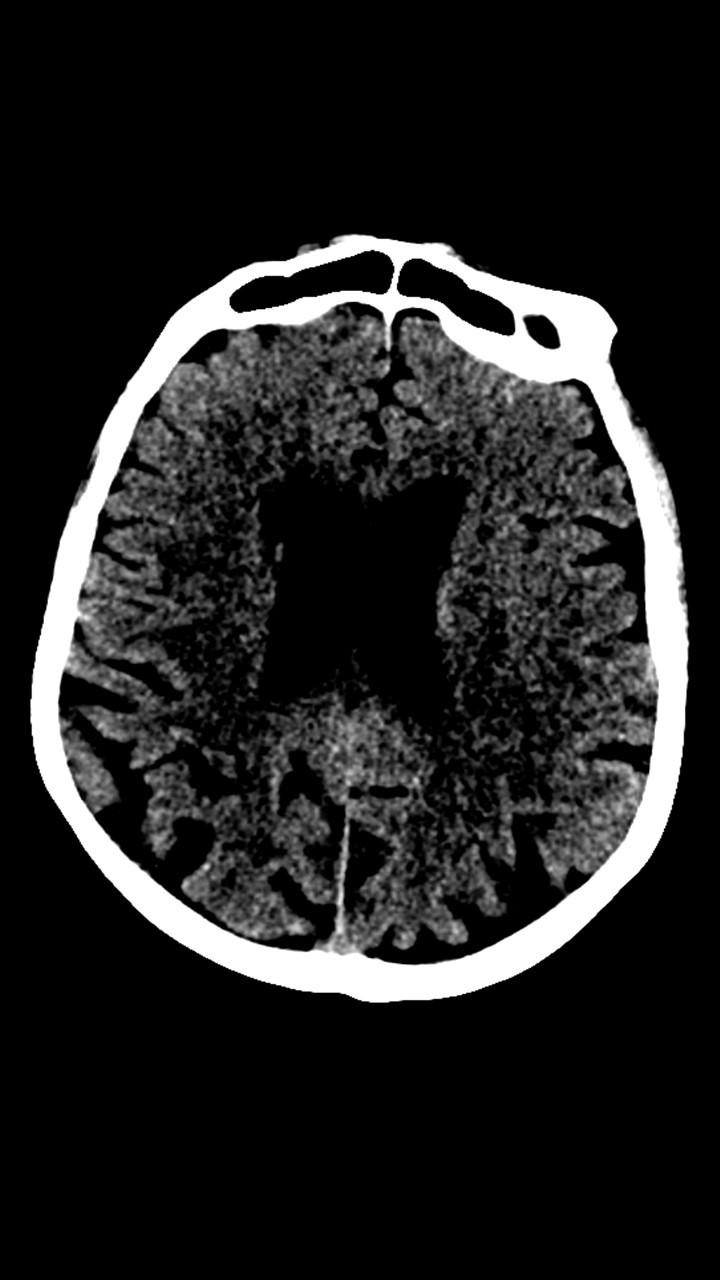

Hallazgos de TC de craneo:

• Cambios de leucoaraiosis periventricular.

• Hay zonas de hipodensidad subcortical fronto-parietal superior predominantemente izquierdas, de aspecto inespecíficos.

• Los halazgos son inespecificos, ante la ausencia de patología hemorragica aguda se decide continuar con el protocolo habitual.